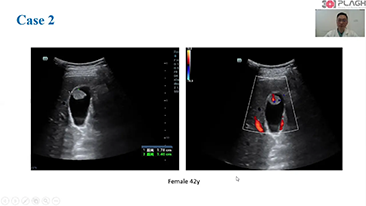

Imagem geral

As solu??es de imagem geral Mindray Resona ajudam mĂŠdicos a obter resultados mais precisos e eficientes de diagnĂłstico e tratamento por meio de sondas de aplica??o de subdivis?es abrangentes e ferramentas eficientes de aplica??o clĂnica.

Produtos para imagem geral